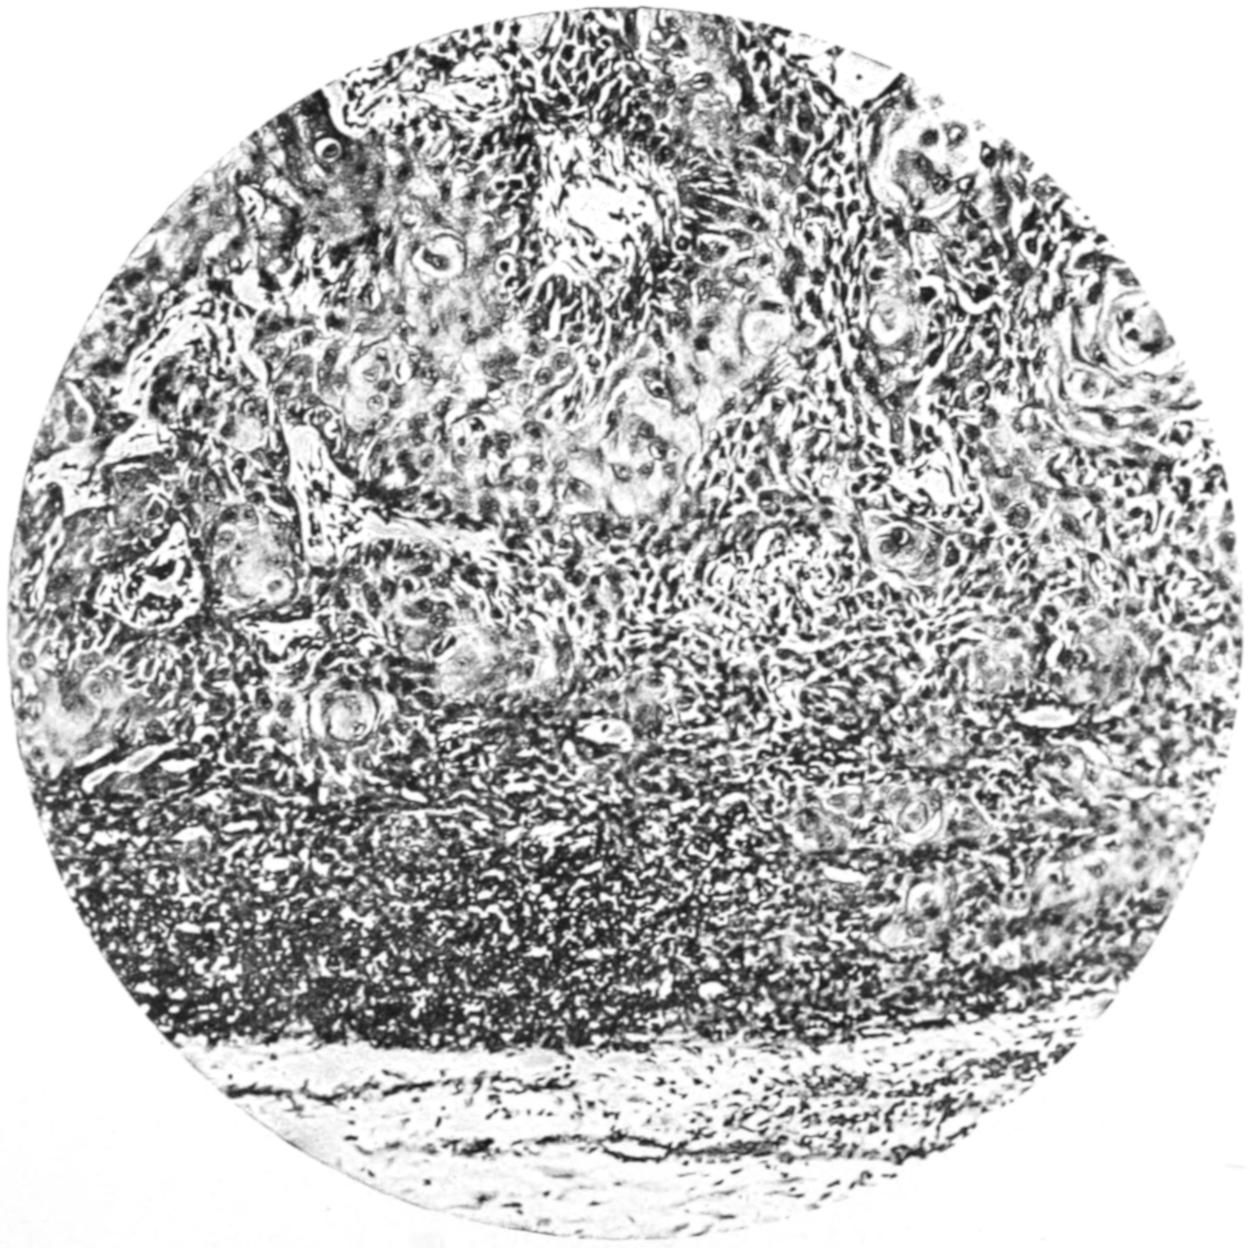

PLATE I

Fig. I.

Fig. II.

Fig. III.

Fig. IV.

Fig. V.

Fig. VI.

Fig. VII.

Fig. VIII.

DRAWN BY J. N. Z. CHASE

PLATE I.

BLOOD.

(Ehrlich triple stain.)

(Prepared by Dr. I. P. Lyon.)

Fig. I. TYPES OF LEUCOCYTES.

a. Polymorphonuclear Neutrophile. b. Polymorphonuclear Eosinophile. c. Myelocyte (Neutrophilic). d. Eosinophilic Myelocyte. e. Large Lymphocyte (large Mononuclear). f. Small Lymphocyte (small Mononuclear).

Fig. II. NORMAL BLOOD.

Field contains one neutrophile. Reds are normal.

Fig. III. ANÆMIA, POST-OPERATIVE (secondary).

The reds are fewer than normal, and are deficient in hæmoglobin and somewhat irregular in form. One normoblast is seen in the field, and two neutrophiles and one small lymphocyte, showing a marked post-hæmorrhagic anæmia, with leucocytosis.

Fig. IV. LEUCOCYTOSIS, INFLAMMATORY.

The reds are normal. A marked leucocytosis is shown, with five neutrophiles and one small lymphocyte. This illustration may also serve the purpose of showing the leucocytosis of malignant tumor.

Fig. V. TRICHINOSIS.

A marked leucocytosis is shown, consisting of an eosinophilia.

Fig. VI. LYMPHATIC LEUKÆMIA.

Slight anæmia. A large relative and absolute increase of the lymphocytes (chiefly the small lymphocytes) is shown.

Fig. VII. SPLENO-MYELOGENOUS LEUKÆMIA.

The reds show a secondary anæmia. Two normoblasts are shown. The leucocytosis is massive. Twenty leucocytes are shown, consisting of nine neutrophiles, seven myelocytes, two small lymphocytes, one eosinophile (polymorphonuclear) and one eosinophilic myelocyte. Note the polymorphous condition of the leucocytes, i. e., their variations from the typical in size and form.

Fig. VIII. VARIETIES OF RED CORPUSCLES.

a. Normal Red Corpuscle (normocyte). b, c. Anæmic Red Corpuscles. d-g. Poikilocytes. h. Microcyte. i. Megalocyte. j-n. Nucleated Red Corpuscles. j, k. Normoblasts. l. Microblast. m, n. Megaloblasts.

The value of a careful blood examination is well illustrated by Plate I, prepared by Dr. Irving P. Lyon, in which are displayed the alterations of greatest interest to the surgeon.